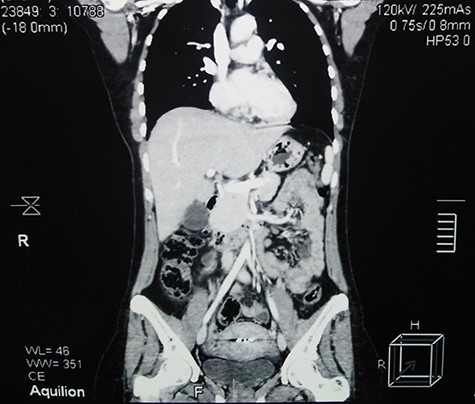

The post-operation period was uneventful and 5-month follow-up, which consisted of a single CT scan and regular clinical examinations, showed no evidence of recurrence (Fig. 4).

Contrast-enhanced abdominal CT scan 5 months after surgery shows full recovery and no evidence of recurrence.

In UCD, surgery is usually curative in which the lesions are removed completely or partially [3]. Furthermore, systemic steroids may provide symptomatic relief, and radiation therapy could be considered. Prognosis in UCD is excellent and patients are usually cured after lymph node excision. Patients may develop lymphoma and/or paraneoplastic pemphigus which could lead to fatal consequences for UCD patients [8]. Regarding this case, removing the mass completely showed acceptable results and 5-month follow-up after surgery showed no evidence of recurrence.